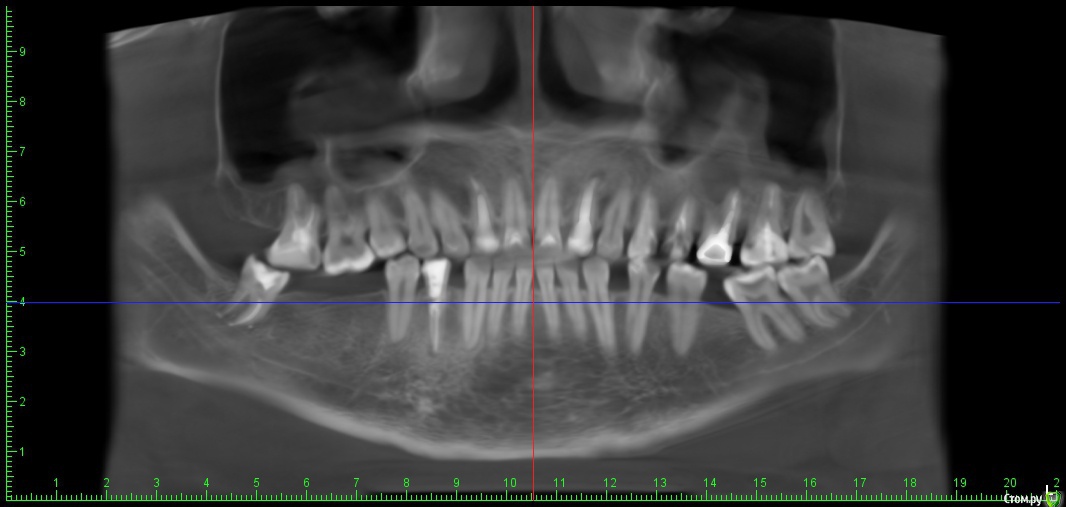

klemento Опубликовано 28 ноября, 2019 Поделиться Опубликовано 28 ноября, 2019 Здравствуйте. Подскажите пожалуйста. Я долго (лет 6) ходил с удаленными нижними 6 и одной 7. Сместились соседние зубы в их сторону с одной стороны. Доктора сначала советуют ставить брекеты и удалять 8. Чтобы выровнять прикус и раздвинуть зубы с 1 стороны, а так же поднять верхние над дырками. Правильный ли это подход? Или сначала возможное протезировать, а потом брекеты? Ссылка на комментарий

klemento Опубликовано 28 ноября, 2019 Автор Поделиться Опубликовано 28 ноября, 2019 (изменено) Извините. Вот КТ. 26 удален. 27 25 под вопросом. Так же щелкает челюсть справа и слева могу щелкать самостоятельно.https://drive.google.com/open?id=1f2ptFqgFpPtr9B8FsYOVlTv_BBs7ex2j Изменено 28 ноября, 2019 пользователем klemento Ссылка на комментарий

red_butler Опубликовано 29 ноября, 2019 Поделиться Опубликовано 29 ноября, 2019 Здравствуйте. Подскажите пожалуйста. Я долго (лет 6) ходил с удаленными нижними 6 и одной 7. Сместились соседние зубы в их сторону с одной стороны. Доктора сначала советуют ставить брекеты и удалять 8. Чтобы выровнять прикус и раздвинуть зубы с 1 стороны, а так же поднять верхние над дырками. Правильный ли это подход? Или сначала возможное протезировать, а потом брекеты?[/size]Вам все правильно говорят Ссылка на комментарий